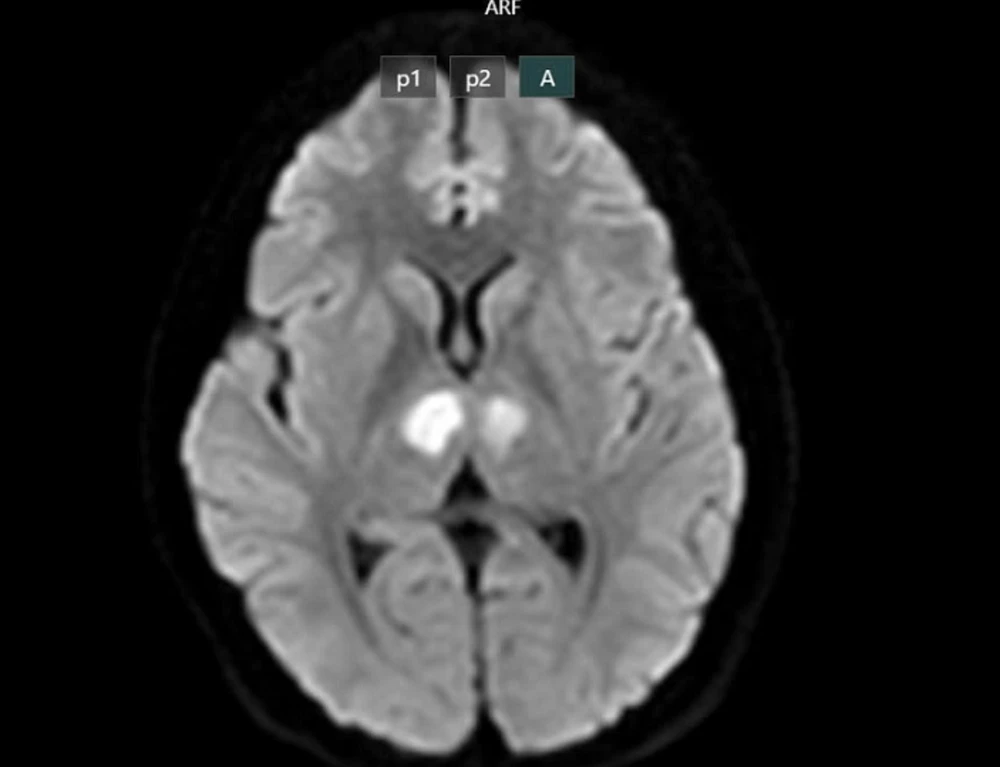

Bệnh nhân được người nhà phát hiện trong tình trạng bất tỉnh, gọi hỏi không đáp ứng, được đưa đến bệnh viện tư để cấp cứu. Kết quả chụp MRI cho thấy não bệnh nhân có hình ảnh tổn thương vùng đồi thị hai bên. Gia đình xin chuyển bệnh nhân đến Bệnh viện Bạch Mai để tiếp tục điều trị.

Não của bệnh nhân bị tổn thương sau 1 tháng dùng thuốc giảm cân không rõ nguồn gốc. Ảnh: BVCC